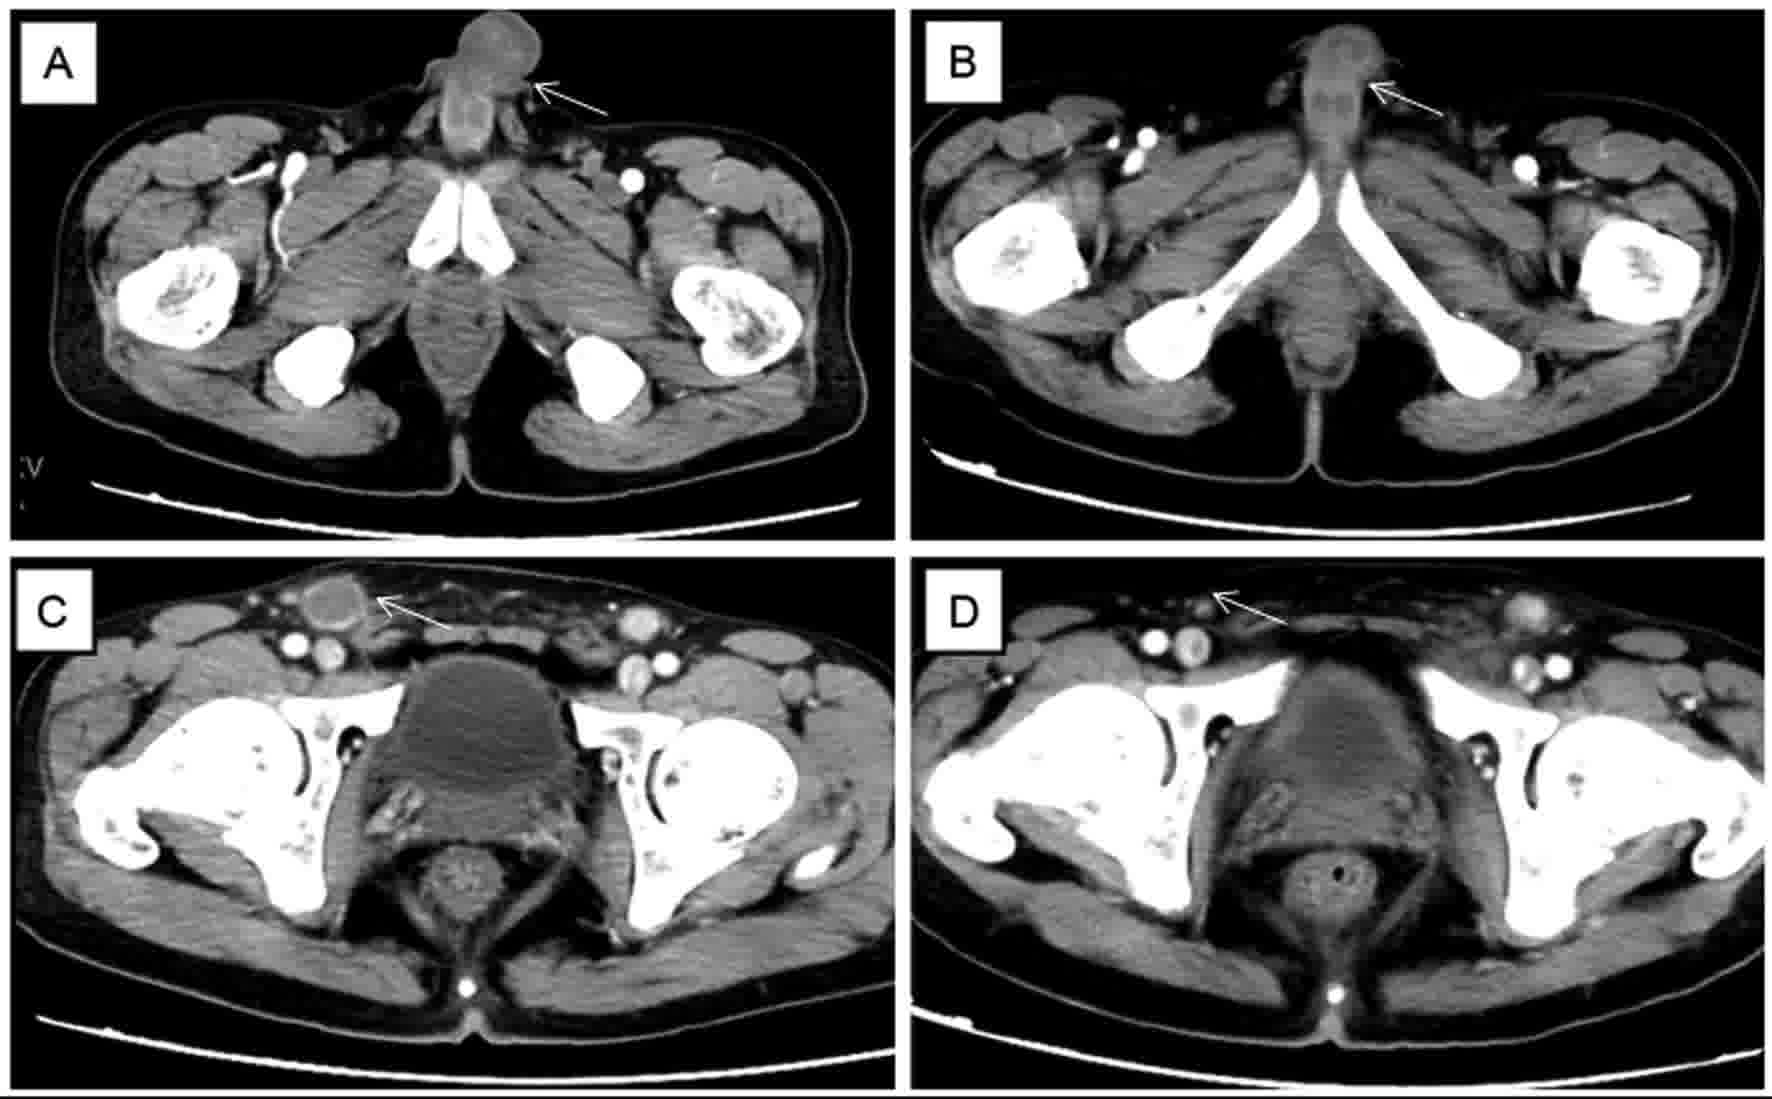

Subsequently, the patient presented with a painless indurated mass in the glans penis that had been present for 1 week. No fever, weight loss or night sweats were reported. The patient denied having had unprotected sexual intercourse, previous sexually transmitted diseases or recent trauma. The physical examination revealed a firm mass affecting the glans penis, without ulceration or swelling, and multiple enlarged palpable lymph nodes in the bilateral inguinal regions. The results of a blood test and biochemical analyses, including an analysis of Epstein-Barr virus (EBV) DNA copies, were in the normal ranges. Enhanced CT showed a soft tissue mass with obscure boundaries and moderate enhancement on the arterial phase, and enlarged inguinal lymph nodes with ring-like enhancement (Fig. 1). An incisional biopsy of the penis was performed as described previously, which led to a diagnosis of penile metastasis secondary to NKTL. Immunohistochemical staining revealed that the biopsy tissue was positive for CD3, CD56, CD43, TIA-1, granzyme B and CD-30 (cat no. ZM-0043; OriGene Technologies, Inc.; Fig. 2). Additionally, in situ hybridization analysis revealed positive expression of EBV-encoded RNA (EBER; cat no. ISH-5021; OriGene Technologies, Inc.), the CD20 (Fig. 2) andanaplastic lymphoma kinase staining results were negative, and staining for Ki-67 was positive in 90% of cells. Enhanced CT scans of the nasopharynx, chest and abdomen, an ultrasound scan of the superficial lymph node-bearing region, and bone marrow aspiration were performed, and no other lesions were detected. A diagnosis of recurrent extranodal NKTL was determined. The patient's clinical stage was IIE, and the IPI score was 1.

Figure 1.

Computed tomography scans. (A) The arrow showed a soft tissue mass with obscure boundaries and moderate enhancement in the glans penis on the arterial phase. (C) The arrow showed an enlarged inguinal lymph node with ring-like enhancement. (B and D) The arrows showed the mass and the lymph node regressed following chemotherapy.

The patient then received three cycles of DDGP chemotherapy, consisting of cisplatin (20 mg/m2; days 1–4), dexamethasone (15 mg/m2; days 1–5), gemcitabine (0.8 g/m2; days 1 and 8) and pegaspargase (2,500 IU/m2; day 1). The penile mass decreased in size following the first cycle and a partial remission was achieved. After two cycles of chemotherapy, the mass in the glans penis and the inguinal lymph nodes had regressed (Fig. 1). Following a further cycle of chemotherapy, the patient remained in a stable condition. Follow-up with the patient was not possible as contact was lost following the last chemotherapy treatment.